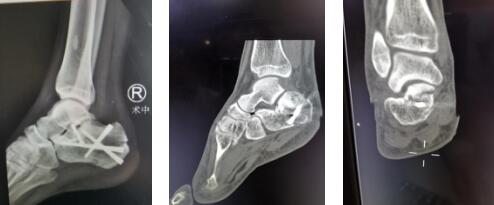

1.3术中关节镜下复位情况

复位前(左图) 复位后(右图)

1.4内固定术后情况